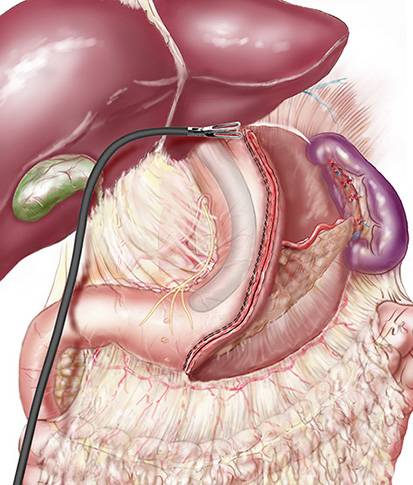

Qu'est ce que la sleeve ?

Parmi les différentes techniques chirurgicales, le groupe MUST propose la sleeve gastrectomie comme un des traitements possibles de l’obésité morbide. C’est une chirurgie de réduction de l’estomac irréversible. Technique purement restrictive, les patients perdent du poids en diminuant les quantité...